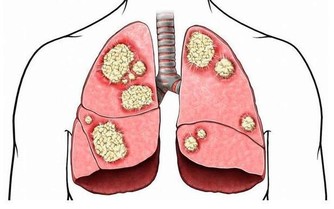

我們就以“燙食”為例,熱乎乎的麵條下肚,穿過胃黏膜,很容易造成胃黏膜收縮甚至破損,為了修復損傷,機體就會在原處繼續生長新的細胞替代,但這個過程並不是十分嚴格,很容易發生錯誤,比如原本應該生長在腸道的細胞過來救急,長在了胃上,這就是化生,是完全錯誤的修補,時間長了,修補面積過多,很容易發展為胃癌。

我曾經受診過一名70多歲的老年患者,最近一段時間總是感覺腹脹,為求保險行胃鏡檢查,發現胃內有大面積的化生,病理結果顯示發現癌細胞,於外科緊急手術治療。和家屬討論病情,老伴就提到,老爺子吃了一輩子的燙食,最喜歡吃麵條、喝熱茶,永遠不嫌飯燙嘴。